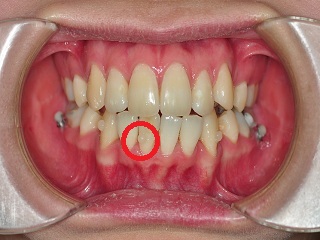

이번 월치료에서는 상악의 와이어교체와 하악 앞니에 보조장치를 부착하였어요.

고르지 못하고 튀어나와있는 하악 앞니에 보조장치를 부착하였습니다.

참 신기한 것이.. 앞니에 보조장치 부착하고 고무줄로 감아 당겨주셨는데,

내려서 거울을 보니깐 툭 튀어나와있던 앞니 한 개가 쏙 들어가잇는거 잇죠 ㅋㅋㅋ

신기했어요 와우 거의 세시간 만에 치아이동이 이루어지다니 @.@